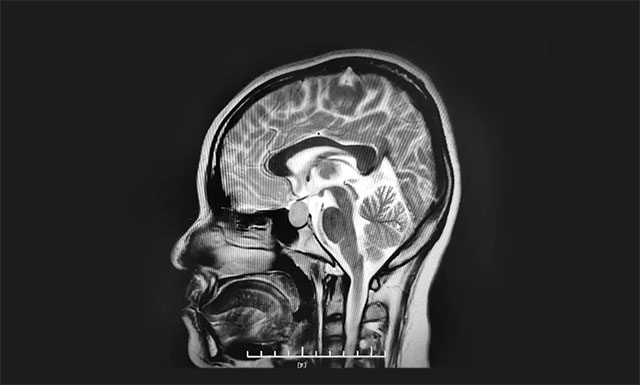

▲ 垂體大腺瘤超蝶鞍生長(zhǎng)

鞍區(qū)MRI平掃+增強(qiáng)顯示:蝶鞍稍擴(kuò)大,鞍底骨質(zhì)下陷;鞍內(nèi)垂體偏左見一枚類橢圓異常信號(hào),大小約1.6*1.4*1.4cm,垂體柄縮短,視交叉上抬。

神經(jīng)外科6B病區(qū)主任潘仁龍主任指出,患者垂體瘤較大,屬于垂體大腺瘤,患者的頭痛和生理期異常就是垂體瘤在作祟。并且腫瘤已經(jīng)壓迫視神經(jīng),手術(shù)指征明確,無(wú)明顯手術(shù)禁忌,應(yīng)及時(shí)手術(shù),否則往后發(fā)展患者視力也會(huì)受損。